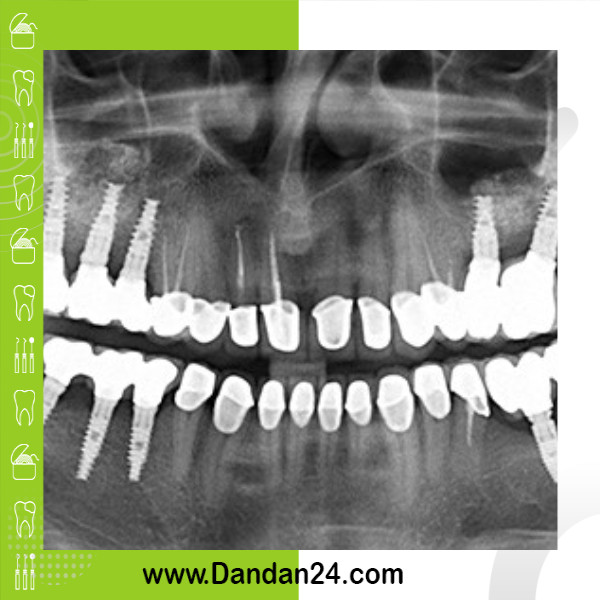

جرمگیری دندان توسط دندانپزشک و با استفاده از ابزارهای مخصوص انجام میشود. در این روش، جرم و پلاک از روی دندانها و زیر لثهها پاک میشود. جرمگیری دندان یک روش ساده و بدون درد است و معمولاً در مطب دندانپزشکی انجام میشود.